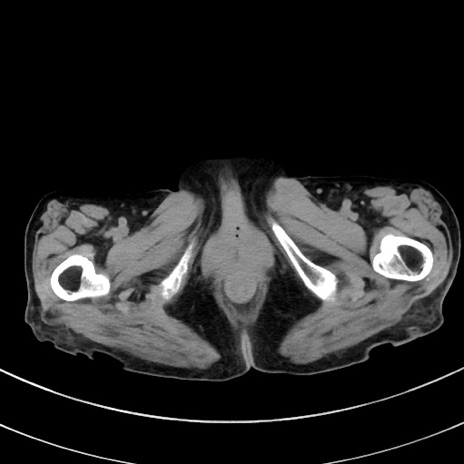

症例33(横断像)

【症例】70歳代 女性

【主訴】心窩部痛

【現病歴】延髄病変の精査・加療にて神経内科入院中。本日より心窩部痛あり。

【身体所見】右下腹部を中心に圧痛と反跳痛あり。

【データ】WBC 10900、CRP 0.02